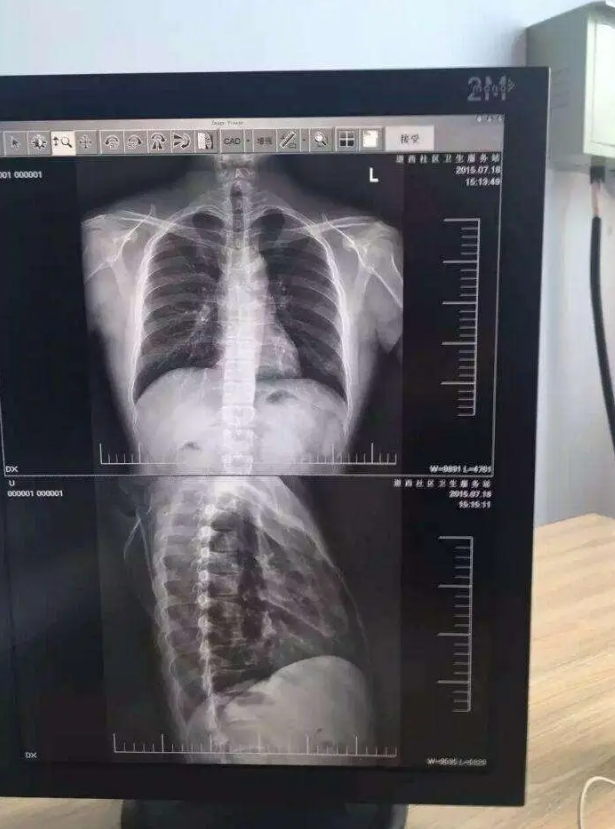

27寸手术室医疗显示器通常具备极高的分辨率,能够呈现出细腻、清晰的影像。在手术过程中,医生需要清晰地观察患者的解剖结构、病变部位以及手术器械的精确位置。高分辨率的显示器可以确保每一个细节都清晰可见,帮助医生做出准确的判断和操作。例如,在神经外科手术中,医生需要精准地避开神经和血管,27寸显示器所呈现的高清影像能够让医生清晰地分辨出这些细微结构,大大提高了手术的安全性;

手术室的光线环境较为复杂,为了确保医生在任何情况下都能清晰地看到影像,27寸医疗显示器具有高亮度和高对比度的特点。高亮度可以保证在明亮的环境下影像依然清晰可见,而高对比度则能够突出影像中的细节,使医生更容易分辨不同的组织和结构。在心脏介入手术中,医生需要在X光影像的引导下进行操作,高亮度和高对比度的显示器能够清晰地显示血管和导丝的位置,为手术的顺利进行提供有力支持。